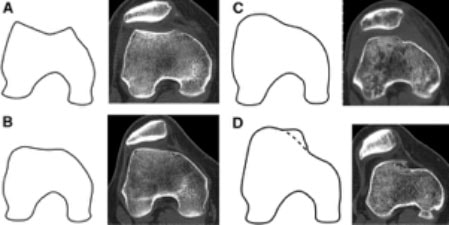

The abnormal loading may be caused by non-modifiable morphological abnormalities. According to Ward et al, patella alta increases the incidence of lateral displacement, lateral tilt, and decreased contact area. As to PFJ contact area, subjects with PA and those with normal patella vertical displacement showed statistically significant difference at all ranges tested (0, 20, 40, and 60of knee flexion).

This makes sense considering that the inferior pole of the patella is thought to make initial contact with the femoral trochlea at about 20 of knee flexion. If the patella is positioned more superiorly, initial contact will not occur until deeper ranges of knee flexion, thus decreasing overall PFJ contact area.

2. Trochlear Dysplasia

Another non-modifiable factor is trochlear dysplasia with corresponding lateral displacement and smaller contact area.This bony morphological defect results in flattening of the lateral facet of the intercondylar groove, which is typically the main local factor controlling excessive lateral patella translation. This can result in the following:

Abnormal loading

Recurrent (even possibly chronic) subluxation dislocation

Up to a 55% decrease in medial patellar stability